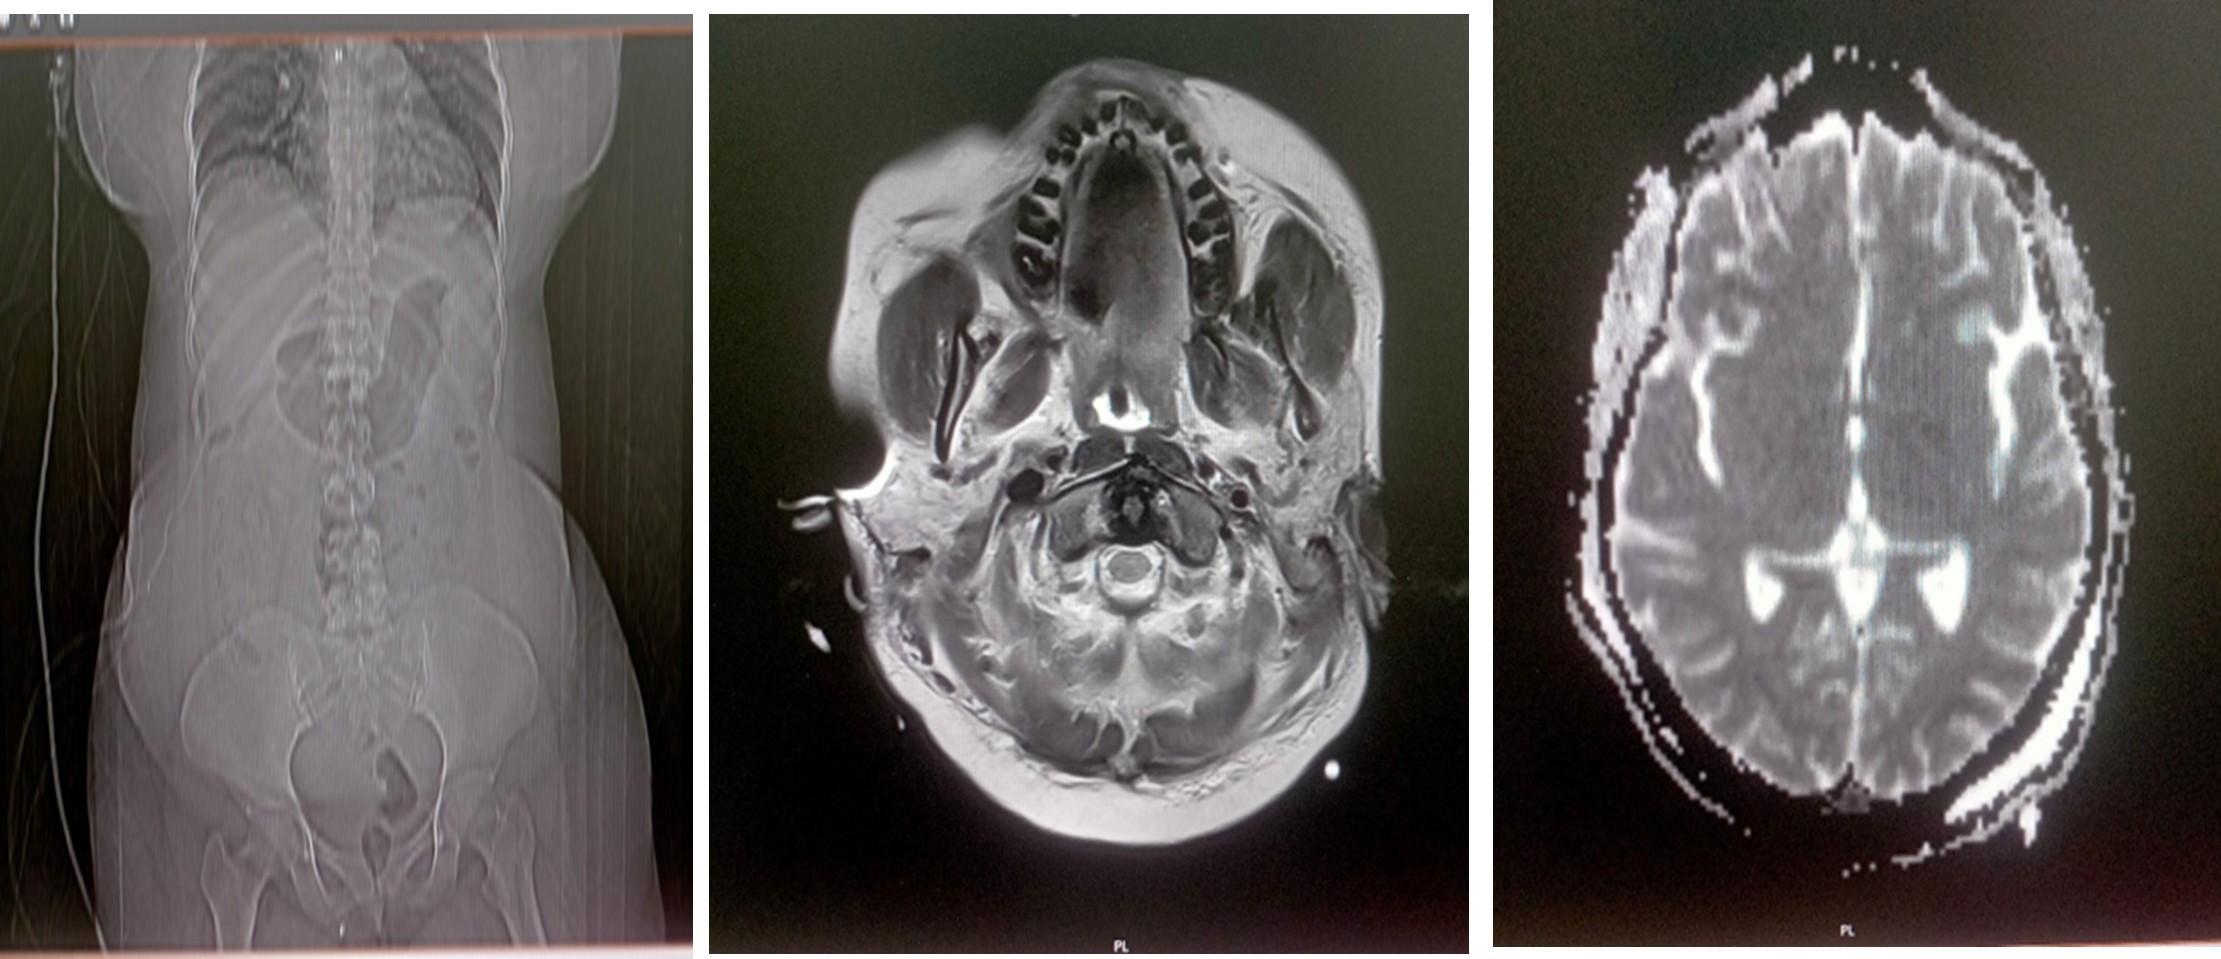

EEG Report (11.02.2026)

This EEG record suggests diffuse cerebral dysfunction.

MRI Brain Plain Report (14.02.2026)

T2/Flair hyperintensities bilateral thalami with patchy areas of diffusion restriction? Hypoxia.

On arrival at our emergency room, her sensorium was irritable and restless; she was tachycardic, tachypnoeic, hypothermic, and had peripheral cyanosis that was more in the right upper limb. Saturation was not recordable and her blood pressure was 60/40 mm Hg. Necessary laboratory investigations, including cultures, were sent. Bedside ultrasonography with echocardiography showed good left‑ventricular contractility with a collapsed inferior vena cava. Treatment was initiated with non‑invasive ventilation, broad‑spectrum antibiotics (Meropenem), adequate intravenous fluid resuscitation, inotropes, antipyretics, and other supportive measures. Arterial blood gas analysis revealed severe metabolic acidosis with high lactate levels. After initial stabilization with IV fluids and inotropes BP improved, saturation stabilized with NIV. The patient was shifted to the ICU for further management. Initial laboratory investigations showed severe anemia, elevated procalcitonin, leukocytosis with severe thrombocytopenia, and deranged renal and liver function tests. Contrast‑enhanced CT of the abdomen demonstrated bilateral renal cortical necrosis, a bulky left rectus abdominis muscle with an intramuscular haematoma and active bleeding, and a bulky uterus. In the ICU she was intubated electively. Empirical tigecycline was added. Her HB- 8.2, Fibrinogen – 108, platelets – 27000. Gynecologist and Surgeon were involved, and the plan was to manage the haematoma conservatively by stabilizing coagulopathy with blood products and to reassess it later. All her blood counts were monitored regularly and were corrected with PRBC, FFP, Cryo and Single donor platelets. In view of acute kidney injury with oliguria and refractory metabolic acidosis, the first session of hemodialysis was performed on 06/02/2026. She also, during this initial course of stabilization, developed severe left‑ventricular dysfunction probably secondary to stress cardiomyopathy. Her FiO₂ requirement increased gradually, and lung ultrasonography showed features of ARDS. Her shock worsened, requiring very high dual inotropic support. Repeating ultrasound later showed no increase in the size of the haematoma. The patient had severe sepsis with multiorgan dysfunction and refractory shock. Shock was refractory for more than 24 hours with high FiO2 requirement. Her peripherals were cold and cyanotic. Hematologist, gastroenterologist, obstetrician‑gynaecologist, cardiologist, and nephrologist were involved in the care. Gradually the patient’s haemodynamics improved; dual inotropic support was tapered and stopped, and the FiO₂ requirement fell. Blood cultures grew in Serratia; Meropenem continued. Empirical teicoplanin was added later. She required regular haemodialysis. Distal gangrene of the upper and lower limbs, more on the right side, was noted, probably secondary to severe shock and inotropes. All counts stabilized and coagulopathy improved. With continued treatment the patient gradually improved but continued to have poor sensorium. EEG showed diffuse cerebral dysfunction. MRI of the brain showed hypoxic‑ischemic encephalopathy. A neurologist was involved.